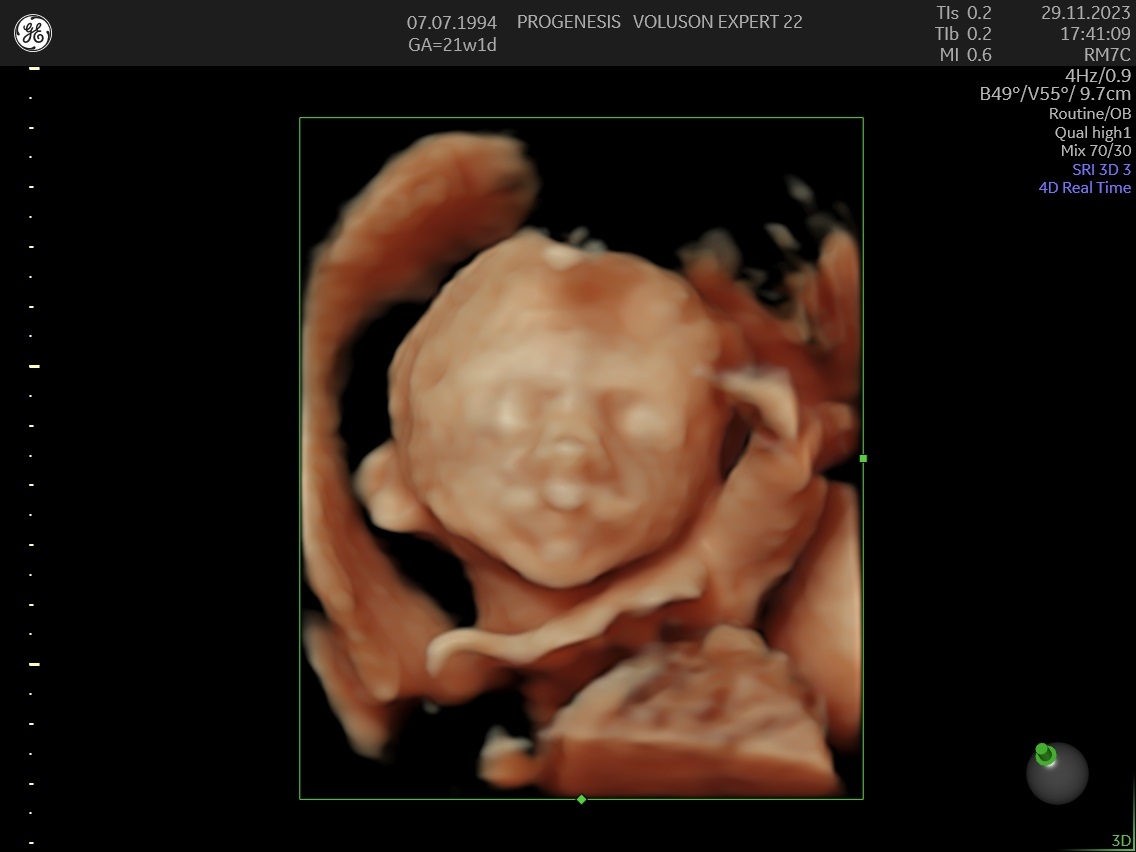

α) Η λεπτομερής αξιολόγηση της εμβρυϊκής ανατομίας, όπου αναγνωρίζονται τυχόν ανατομικές ανωμαλίες.